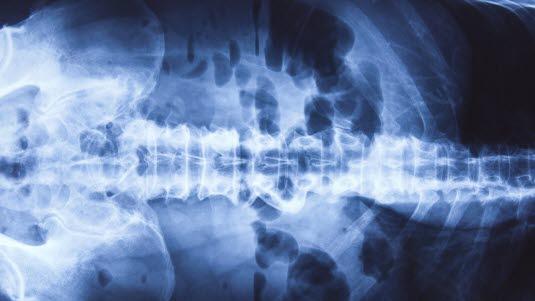

Røntgen oversikt bukhulen

Røntgen oversikt av bukhulen tas uten bruk av kontrast. Undersøkelsen anvendes som et diagnostisk hjelpemiddel ved akutte sykdommer i bukhulen.

Bukhulen består av mange organer. De største er magesekk, tynntarm, tykktarm, lever, milt, bukspyttkjertel, nyrer, urinveier, urinblære. Alle disse organene består av såkalt bløtvev, slik at ingen av dem vil i detalj kunne fremstilles på røntgenbilder uten bruk av kontrast. Likevel kan oversiktsbilder av bukhulen gi nyttig informasjon da luft og eventuelt avføring i tarmen gir informasjon.

Væskespeil er et fenomen som røntgenlegen studerer nøye. Det dreier seg om tarmavsnitt som er fylte med både luft og væske. Det vil da dannes væskeoverflater som kan ses på bilder tatt med horisontal stråleretning.

Det er røntgen oversiktsbilder av bukhulen som tas uten bruk av kontrast. Undersøkelsen anvendes som et diagnostisk hjelpemiddel ved akutte sykdommer i bukhulen som nyrestein, akutt tarmtilstopning av fordøyelseskanalen, oppfylninger eller sprukne organer. Røntgen oversikt bukhulen er ofte en forundersøkelse før mer omfattende undersøkelser. Den kan også gi informasjon om størrelse, form og posisjon til lever, milt og nyrer.

Ved en normal undersøkelse påvises normale organer. Det vil ses endel luft både i magesekken og i tykktarmen. Tolvfingertarmen (første del av tynntarmen) inneholder også ofte luft og væskespeil. Tynntarmen videre kan ev. også inneholde litt luft. Enkelte korte væskespeil i tynn- og tykktarm kan være normalt. Det skal ikke være luft i bukhulen utenom magetarmkanalen, men hvis det går hull på kanalen et eller annet sted, f.eks. magesekken, kan fri luft påvises som tegn på alvorlig sykdom. Det er fare for utvikling av bukhinnebetennelse (peritonitt), som kan være livstruende.